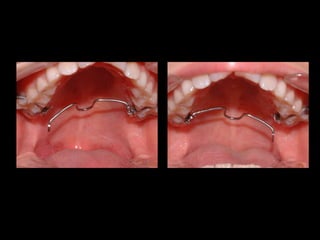

ACTIVACIÓN DE ROTACIÓN DISTAL INSTALAR LA BARRA DE UN LADO EL OTRO EXTREMO DEBE QUEDAR 5MM POR DISTAL DEL TUBO CONTRARIO

LA ACTIVACIÓN  ES CORRECTA CUANDO LA LLAVE LIBRE  SE DESPLAZA  5MM  POR DISTAL DEL TUBO OPUESTO

ACTIVACIÓN DE ROTACIÓNDISTAL INSTALAR LA BARRA DE UN LADO EL OTRO EXTREMO DEBE QUEDAR 5MM POR DISTAL DEL TUBO CONTRARIO